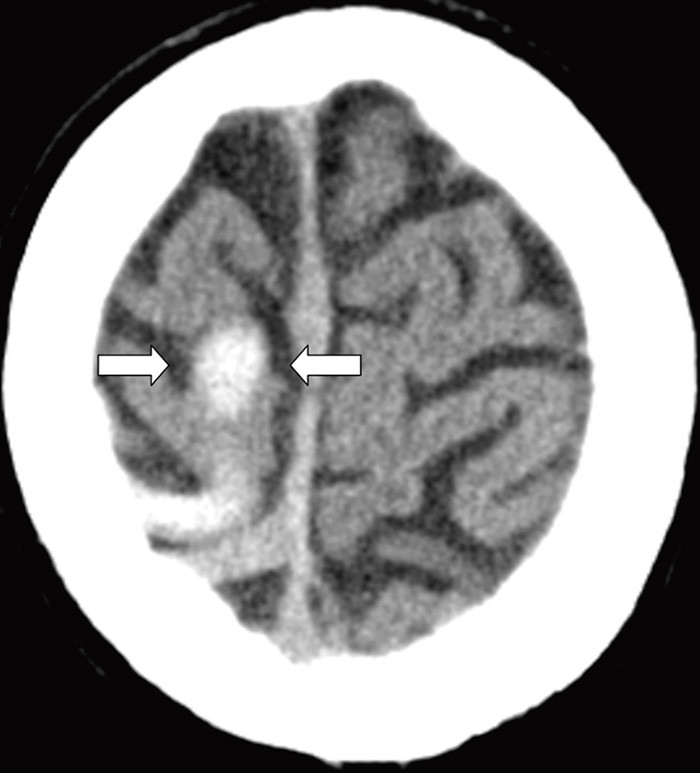

A previously healthy woman in her 40s suffered morning headache and vomiting the day before admission. She was a non-smoker and used no medicines or hormones. On the following day she developed acute left facial paresis, left arm paresis and dysarthria. She experienced transient spasms in the left part of her face. Cerebral CT performed at the local hospital showed a high-attenuation lesion in the right temporoparietal lobe (see online version for picture). D-dimer was 0.8 mg/l (normal < 0.4). A vascular event in the right hemisphere was suspected. Cerebral MR venography at the university hospital the following day revealed an intraluminal venous thrombus corresponding to the right vein of Trolard (left picture). Diffusion-weighted cerebral MRI showed a mix of vasogenous and cytotoxic oedema in the temporoparietal region, typical of a venous infarction (right picture). Tests of thrombocoagulation system function revealed activated protein C resistance 0.66 (normal 0.85 – 1.15). The patient received anticoagulant therapy and six days later follow-up cerebral MR venography showed normalisation. She was discharged without sequelae.

Cerebral venous thrombosis often presents with severe headache and may cause focal neurological impairment and epileptic attacks in the presence of an infarction. Activated protein C resistance predisposes for cerebral venous thrombosis, which is a rare (0.5 – 1 %) cause of cerebral infarction (1). Early diagnosis and treatment are essential for a good clinical outcome. CT and MR venography enable non-invasive visualisation of venous cerebral thrombosis with a high degree of sensitivity and specificity.